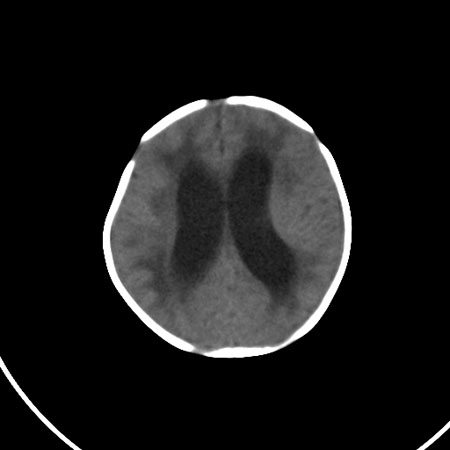

以下是引用小初学者在2009-1-10 17:51:00的发言:[br]考虑缺血缺氧性脑病后遗性改变。

以下是引用拾荒者在2009-1-10 19:23:00的发言:[br]生后有蛛网膜下腔出血病史,现幕上脑室明显扩张,脑室周围白质局限性密度减低,考虑hie脑病后遗表现。